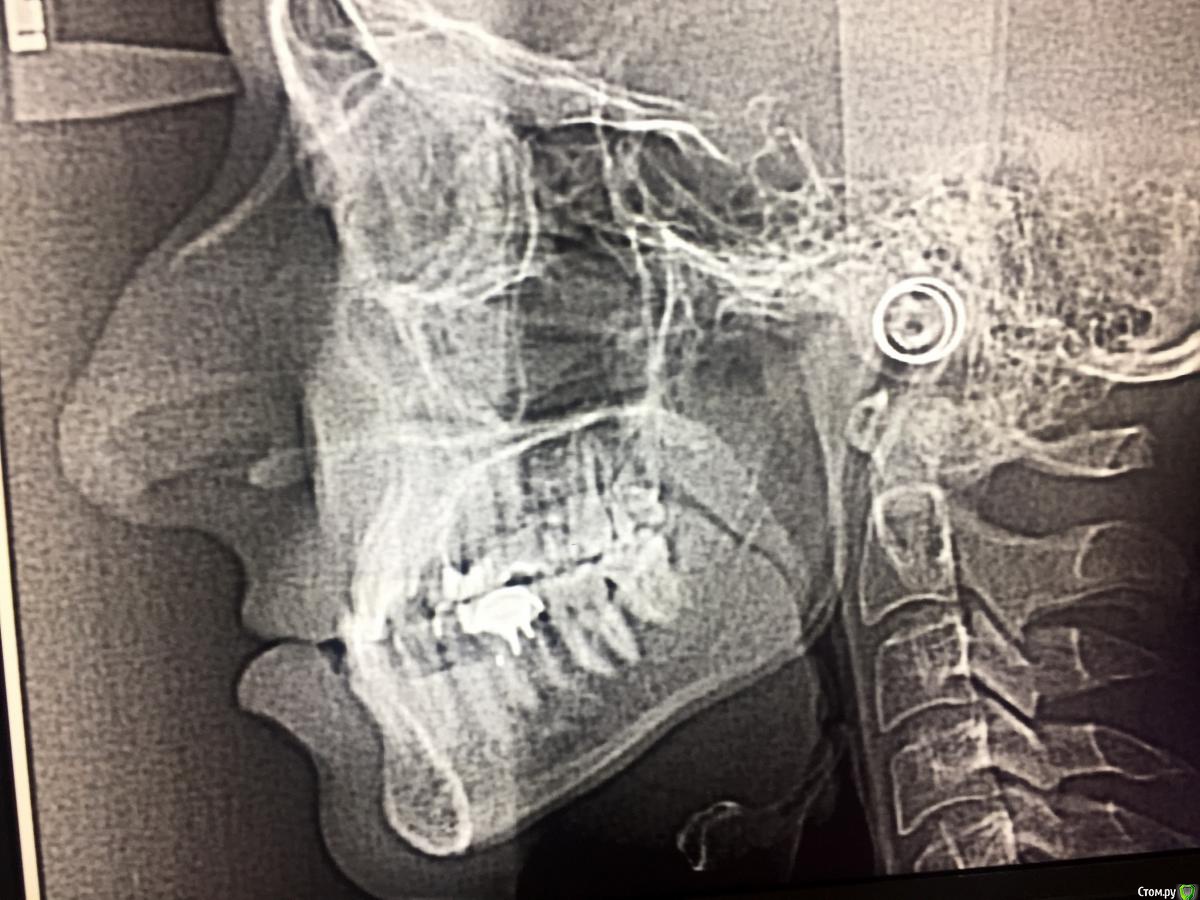

Jackfor18 Опубликовано 6 марта, 2018 Поделиться Опубликовано 6 марта, 2018 Помогите!!!!!!! Друзья, помогите пожалуйста определиться с диазнозом и с вариантами лечения !!!!! Я запутался, а к тем врачам что я ходил, думаю лукавят и не вызывают доверия. Прикус медиальный, но при это нижняя челюсть (подбородок мал)?! Верхняя челюсть при этом крупнее нижней, и всё равно её нужно расширять? Аппарат Дерихсвайлера ? Или оперировать нижнюю челюсть?Друзья, подскжаите советом, голова кругом. Какие варианты лечения?Поможет ли брейкет система? И все таки непонятно какой у меня диагноз до сих пор не разберусь? Заранее спасибо! Ссылка на комментарий